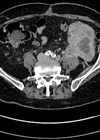

A 64-year-old man presents to the haematuria clinic with visible haematuria, on a background of a 40 pack-year smoking history and family history of bowel cancer in his sister at the age of 48. A CT was performed as part of his investigations (Figure 1).

Figure 1.

Figure 1: Case courtesy of Dr Michael P Hartung, Radiopaedia.org, rID: 78377.

- This is a CT urography (CTU), or CT intravenous urogram (CT-IVU). Most CTU protocols consists of three phases; non-contrast, enhanced / nephrographic, and a delayed / excretory phase. The non-contrast phase is performed prior to contrast administration, the enhanced phase is taken 90-100 seconds after contrast administration and the delayed phase is taken 5-15 minutes after contrast has been given.

- The delayed phase of this CT has demonstrated a filling defect in the left renal pelvis, raising suspicions of UTUC. Other common differential diagnosis includes centrally located renal cancer, benign tumours (e.g. fibroepithelial polyps, nephrogenic adenomas), papillary necrosis, and blood clot.